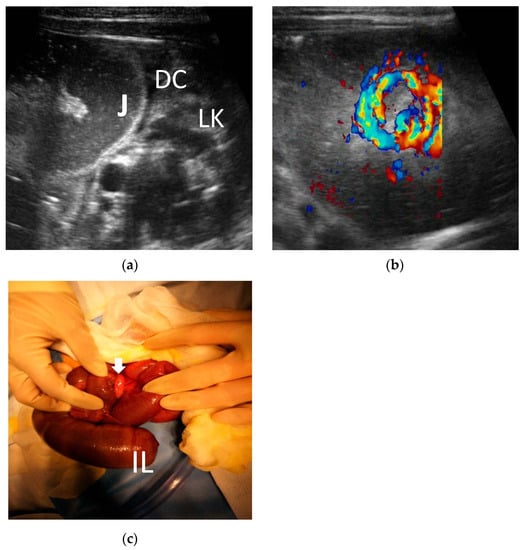

3.2. The Ultrasonic Manifestations

3.2.1. The Ultrasonic Signs of Intestinal Obstruction

3.2.2. The Corresponding Ultrasound Findings of Diseases Leading to Neonatal Ileus